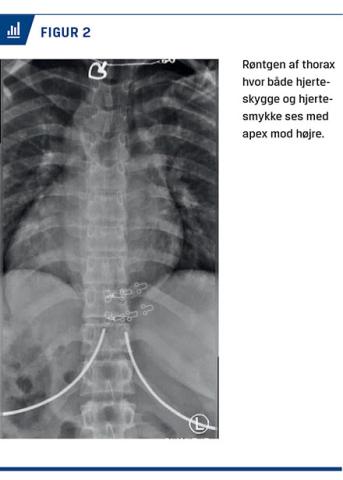

Urinstiks var positiv for blod. På mistanke om sten i urinvejene foretog vi en CT af abdomen uden kontrast. Ved denne påvistes kun et lille konkrement i venstre pelvis, antageligt var det symptomgivende konkrement afgået. Som bifund så vi intratorakale og -abdominale organer med spejlvendt placering, altså SI totalis (Figur 1).